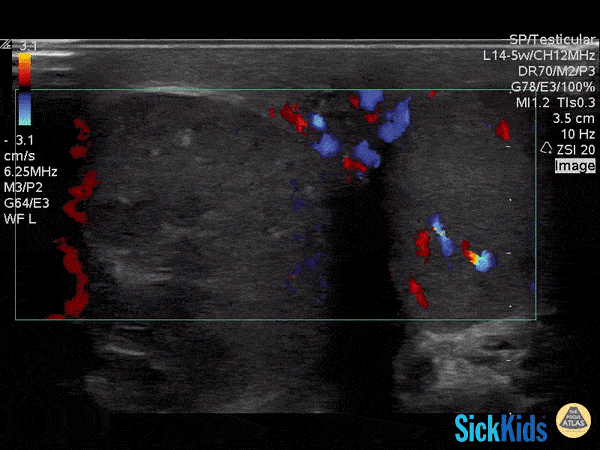

Decreased color doppler is seen in this pediatric patient with testicular torsion. Dr. Lianne McLean (@doctorlianne) FRCPC of the PEM POCUS Group: Division of Emergency Medicine in the Hospital for Sick Children (@epocus)